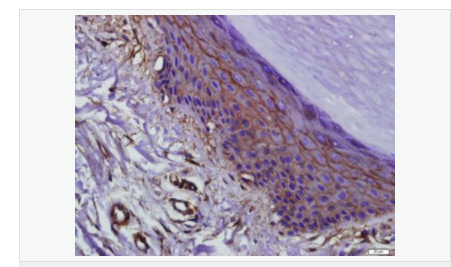

| 產品應用 | WB=1:500-2000 ELISA=1:5000-10000 IHC-P=1:100-500 IHC-F=1:100-500 Flow-Cyt=1μg/Test ICC=1:100 IF=1:100-500 (石蠟切片需做抗原修復) not yet tested in other applications. optimal dilutions/concentrations should be determined by the end user. |

| 產品介紹 | This gene encodes an integral membrane protein which is located at tight junctions. This protein may be involved in the formation and maintenance of the tight junction. The possibility of several alternatively spliced products has been suggested but the full nature of these products has not been described. [provided by RefSeq]. Function: May play a role in the formation and regulation of the tight junction (TJ) paracellular permeability barrier. Subunit: Interacts with TJP1/ZO1 and with VAPA. Subcellular Location: Membrane; Multi-pass membrane protein. Cell junction, tight junction. Tissue Specificity: Localized at tight junctions of both epithelial and endothelial cells. Highly expressed in kidney. Not detected in testis. Post-translational modifications: Phosphorylated upon DNA damage, probably by ATM or ATR. Dephosphorylated by PTPRJ. May be phosphorylated by PKC during translocation to cell-cell contacts. Similarity: Belongs to the ELL/occludin family. Contains 1 MARVEL domain. SWISS: Q16625 Gene ID: 100506658 Database links: Entrez Gene: 18260 Mouse Entrez Gene: 100506658 Human Omim: 602876 Human SwissProt: Q16625 Human SwissProt: Q61146 Mouse Unigene: 592605 Human Unigene: 4807 Mouse Unigene: 31429 Rat Important Note: This product as supplied is intended for research use only, not for use in human, therapeutic or diagnostic applications. |